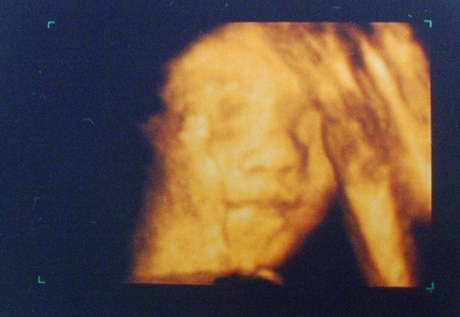

[第二次4D超音波-31w3d]

今天是照第二次4D超音波的日子,

沒想到小菜包卻意外的賞臉,今天把臉轉過來了....

我家小菜包可愛的臉~.

*偷偷睜開眼睛,護士講的時候我還沒發現哩,右眼有偷偷瞇開。

*才誇獎他今天好乖,沒想到馬上手就來了,還把手指頭塞進嘴裡。

手指頭還滿修長的說...XD。